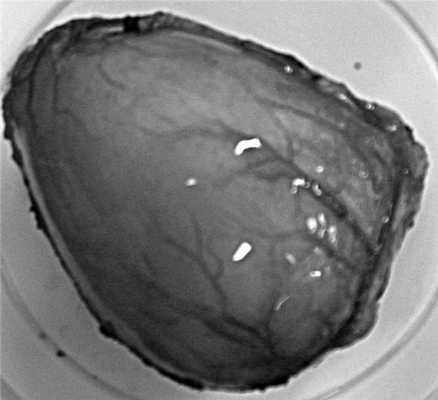

Макропрепарат: частично вскрытое кистозное образование диаметром 9 см. Наружная поверхность образования с инъецированными сосудами, гладкая, внутренняя - шероховатая с полиповидным образованием диаметром 1,5 см. На отдельных участках стенки кисты имеются кальцинаты. С наружной стороны к стенке кистозного образования интимно прилежит резецированная часть желудка. Макроскопически полость желудка и кисты не связана.

Гистологическое исследование: стенка кисты построена из фиброзной и гладкой мышечной ткани с поперечно и продольно ориентированными пучками волокон (рис. 2 на цв. вклейке). Рисунок 2. Микрофотографии. а - продольно и поперечно ориентированные пучки волокон гладкой мышечной ткани в стенке ДК желудка. Окраска гематоксилином и эозином, ув. 50; б - атрофичный однослойный однорядный эпителий, выстилающий внутреннюю поверхность ДК. Окраска гематоксилином и эозином, ув. 400; в - аденокарцинома кишечного типа. Окраска гематоксилином и эозином, ув. 100; г - аденокарцинома кишечного типа. Окраска гематоксилином и эозином, ув. 200; д - мембранная экспрессия пан-цитокератина (клон AE1/AE3) клетками опухоли. Иммунопероксидазный метод, DAB, гематоксилин. Ув. 200; е - экспрессия Ki-67 (клон MIB1) в клетках опухоли. Иммунопероксидазный метод, DAB, окраска гематоксилином. Ув. 200. Во всех слоях имеются очаговая лимфоцитарная инфильтрация и гиалиноз. Внутренняя поверхность кисты с субтотальной атрофией покровного эпителия, на отдельных участках представленного однослойным эпителием, на других - эпителием желудка. Полиповидное образование в средней части препарата имеет строение аденокарциномы кишечного типа, с начальными явлениями инвазии во внутренний мышечный слой кисты. В стенке прилежащего желудка элементов опухоли не обнаружено. При иммуногистохимическом исследовании клетки опухоли негативны к Synaptophysin (SY38), Chromogranin A (DAK-A3), CD56 (123C3) и экспрессируют пан-цитокератин (клон AE1/AE3). Количество пролиферирующих клеток опухолевого субстрата по экспрессии молекулы Ki-67 (клон MIB1) более 60%. Заключение: морфологическая картина дупликационной кисты желудка с малигнизацией.